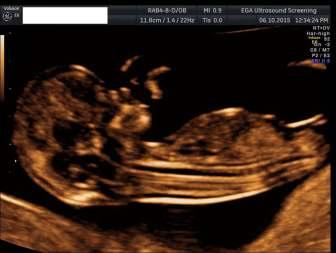

Д-р Борис Стоилов е акушер-гинеколог и специалист по фетална медицина, завършил престижния King's College в Лондон, Великобритания. Той е управител на Център по Майчино-Фетална Медицина в гр. Пловдив и преподавател в Медицински Университет-Пловдив. Можете да си запишете час за преглед на тел. 0876 222 711. Прочетете повече на: http://pregnancy.bg/ Най-разпространената тризомия е на 21-ва двойка хромозоми или Даун синдром, който засяга 1 на 500 бременни в 20 г.с. Други често срещани тризомии са Синдрома на Патау и Синдрома на Едуардс На всеки един от тях се спирам по подробно в следващите редове. Синдром на Даун Даун синдром или тризомия 21 е хромозомна аномалия, при която има добавена още една

на бременността и водят до аборт, а други могат да имат по-голяма преживяемост. Но всички тези тризомии водят до различни отклонения в анатомията, физическото или психическото развитие. Тази аномалия е кръстена на Джон Лангдон Даун, първият учен обяснил нейния произход Синдромът е в положителна корелация с увеличаване на възрастта на жената, особено след 35г. Именно поради това, в миналото, на всички жени, навършили 35г им се предлагаше амниоцентеза Със съвременните методи като комбиниран скрининг и cff DNA, инвазивните методи за откриване на трите най-често срещани тризомии 21, 13 и 18 не трябва да се използват като първо средство, а трябва да има градация на изследванията за намаляване на нежеланите последствия. Медицината като цяло е постигнала сериозен напредък в неинвазивните методи на диагностика, които трябва да бъдат използвани в пълен обем преди инвазивните процедури. Всичко останало е неправилна и некомпетентна намеса с поемане на неоправдан риск. За разлика от повечето тризомии, децата родени с Даун синдром са жизнеспособни. В 50% от случаите на тризомия 21 не могат да се открият ултразвукови маркери за откриването й. При останалите 50% могат да се открият един или множество аномалии Тези маркери могат да са по важни или

основните аномалии са сърдечни аномалии с

изоставане. В голям процент от случаите тези деца преживяват около 20 до 30 години поради множеството аномалии. Тези, които са с умствено изоставане се нуждаят от специални грижи. Сред останалите може да има деца, които да учат и дори да си намерят работа. И тук именно идва въпроса защо трябва да се изследваме за това дали вашето дете може да е с Даун!? Изследването, особено комбинираният скрининг и cff DNA са неинвазивни процедури свързани само с вземане на венозна кръв от бременната жена. Тези методи не носят риск нито за вас, нито за вашето бебе. С тези два метода се прави скрининг също така и за Патау и Едуардс синдроми Откриването на някои от тези синдроми би било изключително полезно както за вас като бъдещ родител, така и за нас медиците. За родителите е важно, защото те ще могат да вземат най-правилното за тях решение - дали да Íàé-÷åñòî ñðåùàíèòå õðîìîçîìíè àíîìàëèè МАМА И БЕБЕ Д-р Борис Стоилов Център по Майчино-Фетална Медицина 33.bgАПТЕКИ